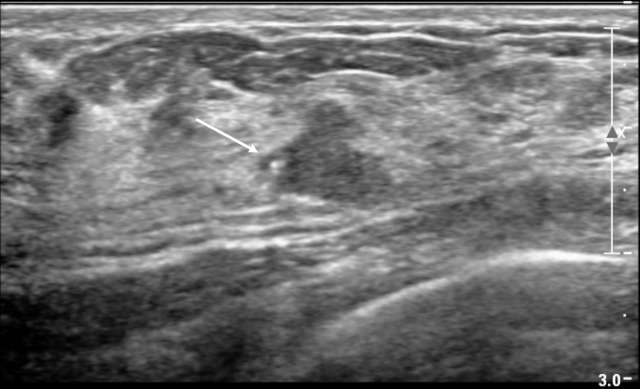

Areas of calcified fat necrosis.

Figure 1. 67 year old woman with remote history of right breast cancer status post surgical excision with areas of calcified fat necrosis (arrow). The calcifications in the fat necrosis contribute to the shadowing seen in ultrasound.